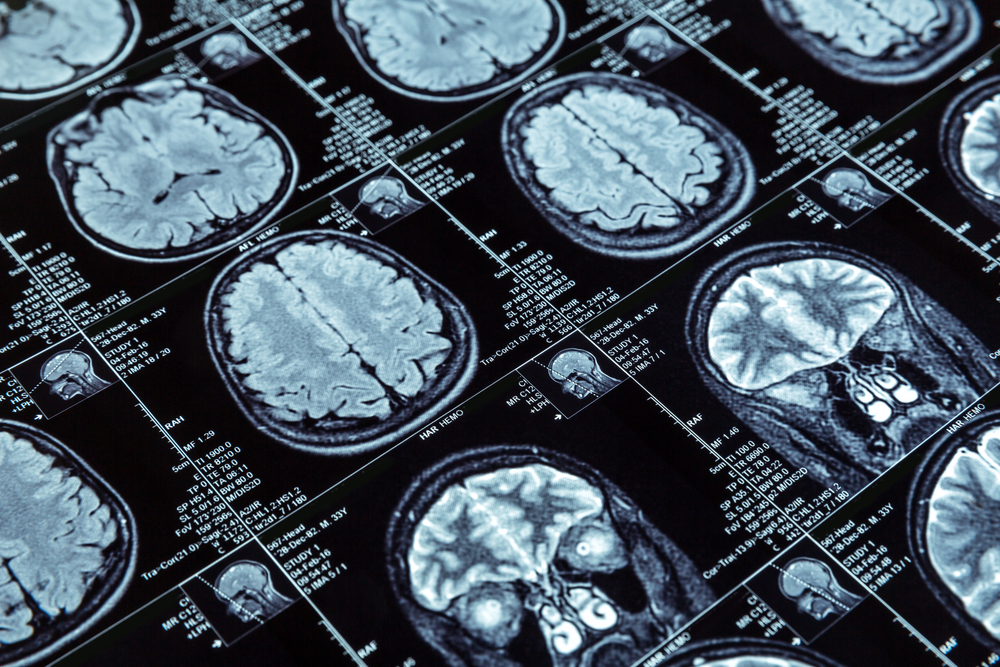

アルツハイマーは潜行する? 発症数十年前から進行の可能性

アルツハイマー病

アルツハイマー病に関する最近の研究により、この記憶障害の病気が脳に与える影響について新たな理解が進んでいます。研究では、症状が現れる数十年前から脳内で重要な変化が始まる可能性が示唆されています。